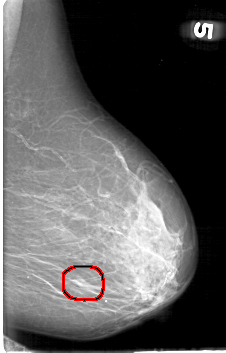

FILE: D_4095_1.LEFT_CC.OVERLAY

TOTAL_ABNORMALITIES 1

ABNORMALITY 1

LESION_TYPE MASS SHAPE ROUND MARGINS OBSCURED

ASSESSMENT 0

SUBTLETY 4

PATHOLOGY BENIGN

TOTAL_OUTLINES 1

BOUNDARY

LEFT_CC LINES 5026 PIXELS_PER_LINE 3331 BITS_PER_PIXEL 12 RESOLUTION 43.5 OVERLAY